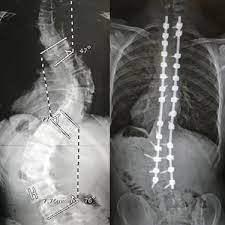

Scoliosis Spine Surgery is done to realign and fuse the curved vertebrae so that they heal into a single, solid bone.

Scoliosis surgeons can improve curves significantly with the tools and technology available today.